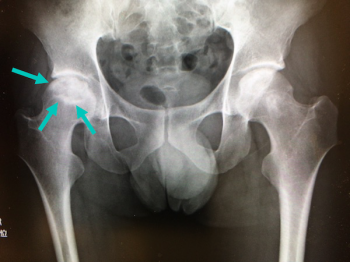

今日、ご紹介するのは、大腿骨の病気 特発性大腿骨頭無腐性壊死についてご紹介していきます。

特発性大腿骨頭無腐性壊死とは

成人の大腿骨頭に明らかな原因がなく、血流の低下により壊死(血が通わなくなって骨組織が死んだ状態)に陥った状態です。

中年の男性に多く、片側に発症するが、数年で70%くらいが両側性になる。

X線、CTスキャン、磁気共鳴画像法(MRI): 骨の変化